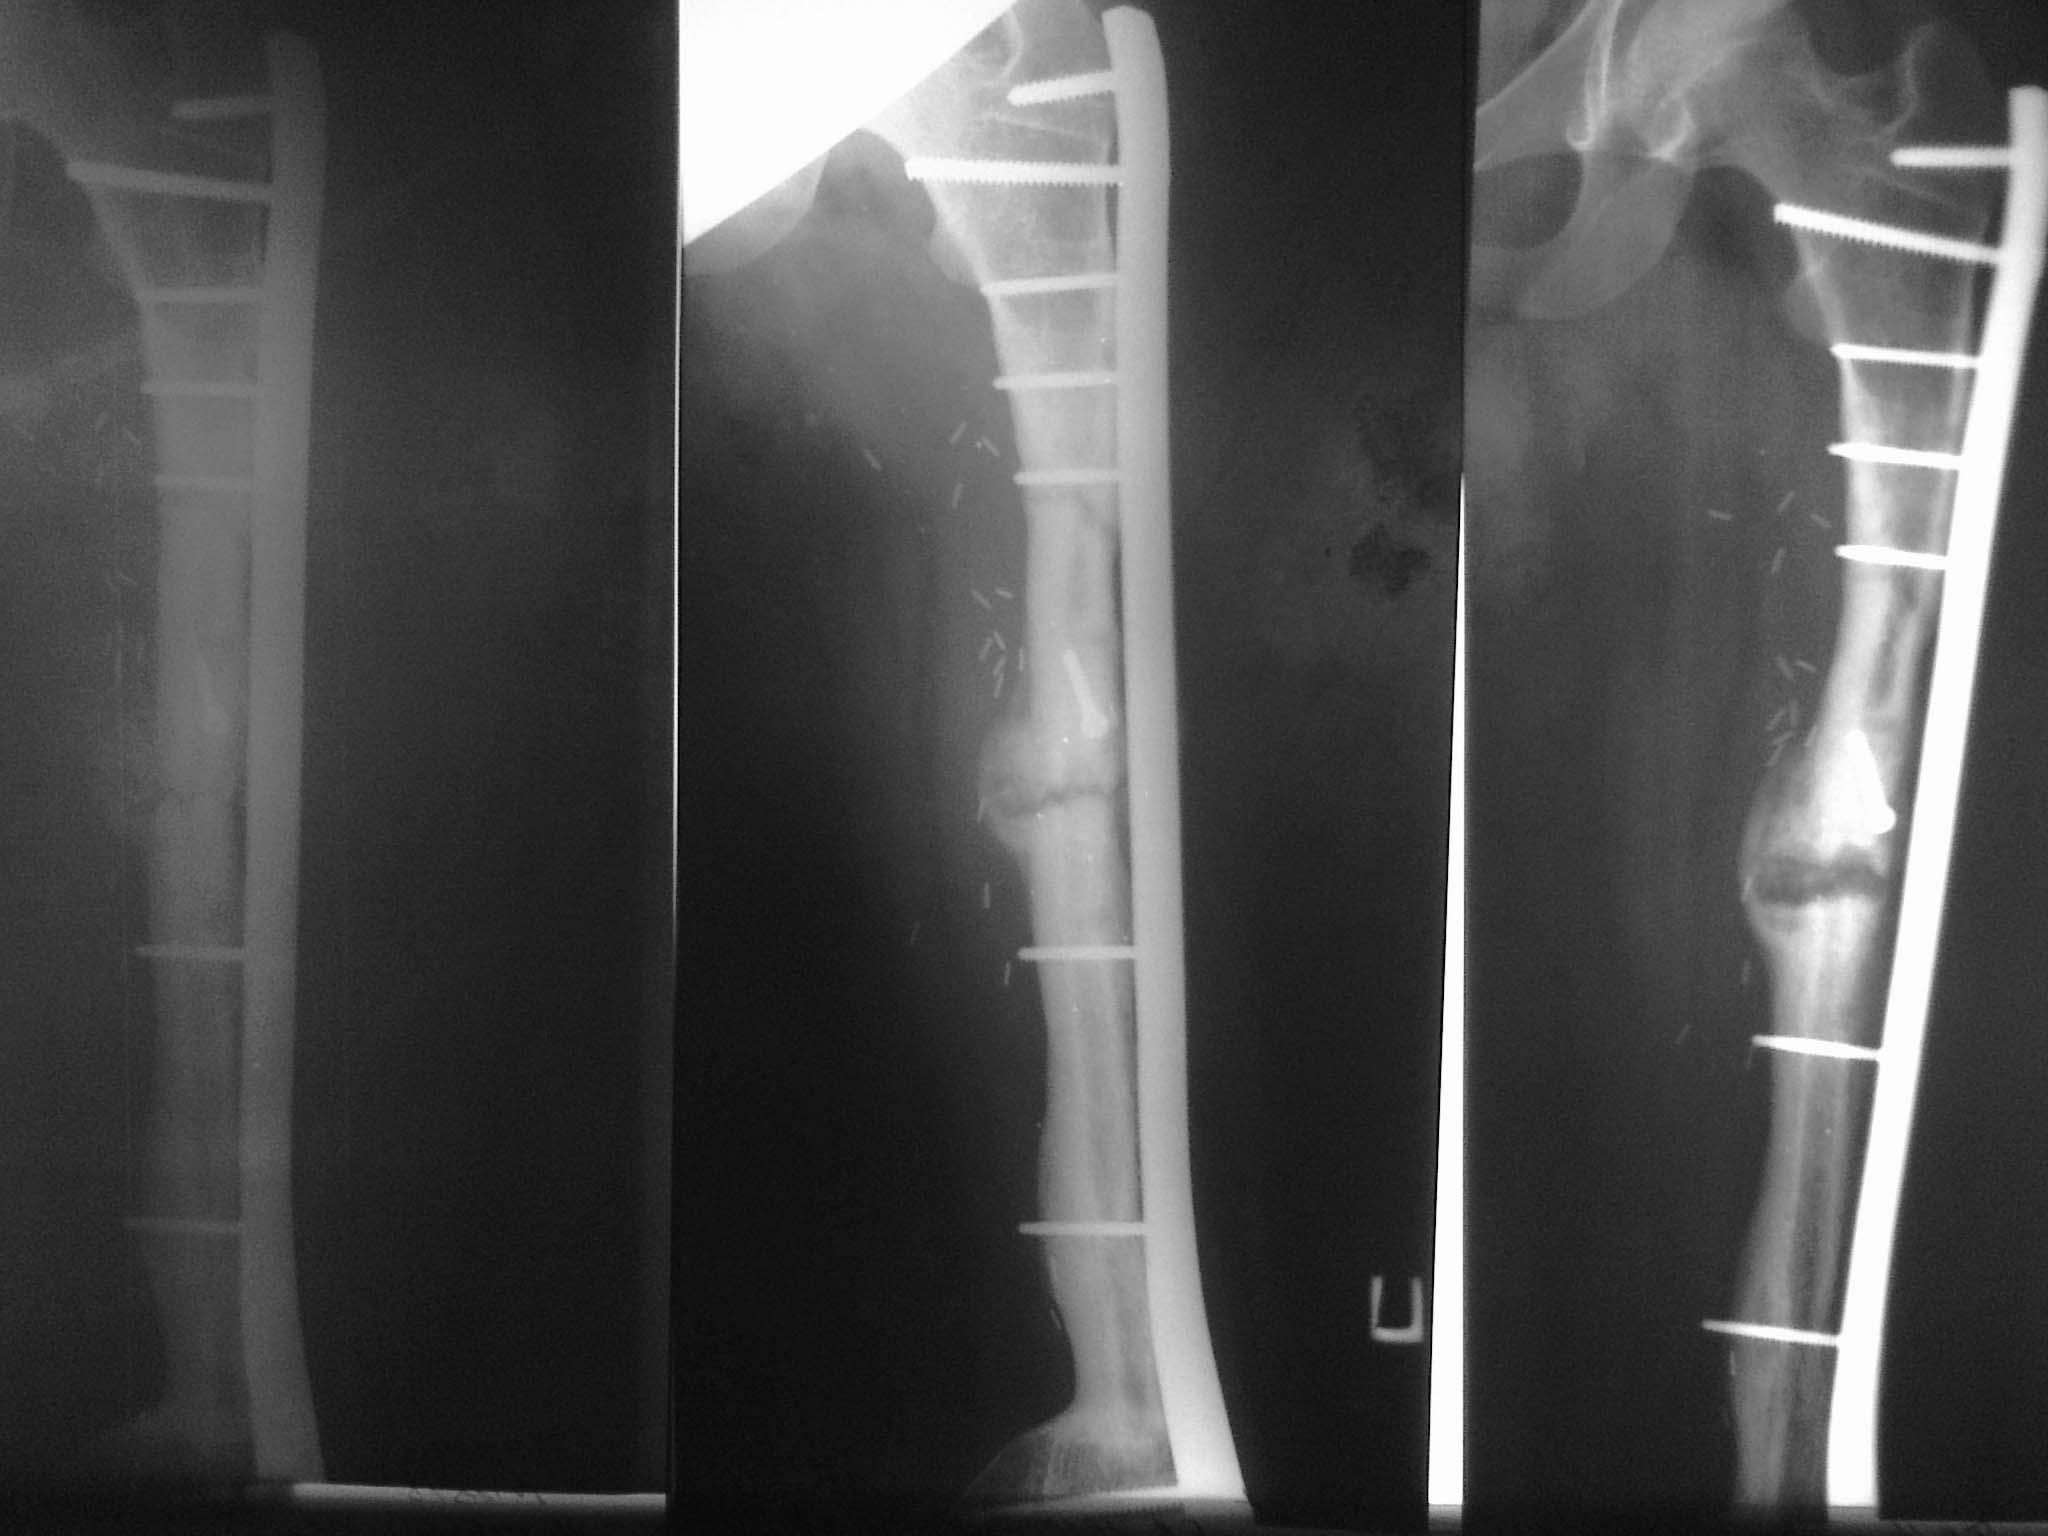

Отправитель: Чернюк Евгений 11 Март 2013, 00:02

Продолжение истории. От биопсии родственники отказались, результат на март (фото) на фоне лечения "Prolia"